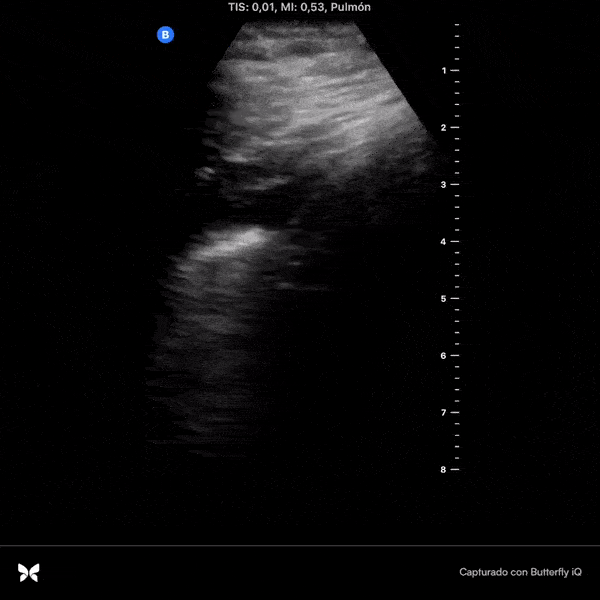

COVID 19 Lung US Disease Progression - Day 2

Day 2 after #COVID diagnosis. Less sore throat, cough & headache (thank God!), still no shortness of breath or pleuritic chest pain. #POCUS update: small bilateral pleural effusion, thickened pleural line & basal b-lines (plaps). @yaletung